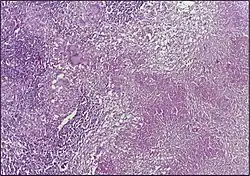

![]() | Dysgerminoma | Dysgerminoma characterized by uniform cells resembling primordial germ cells separated by fibrous septa with lymphocytes. | Category: Histopathology of ovarian dysgerminoma | Ovarian dysgerminoma |